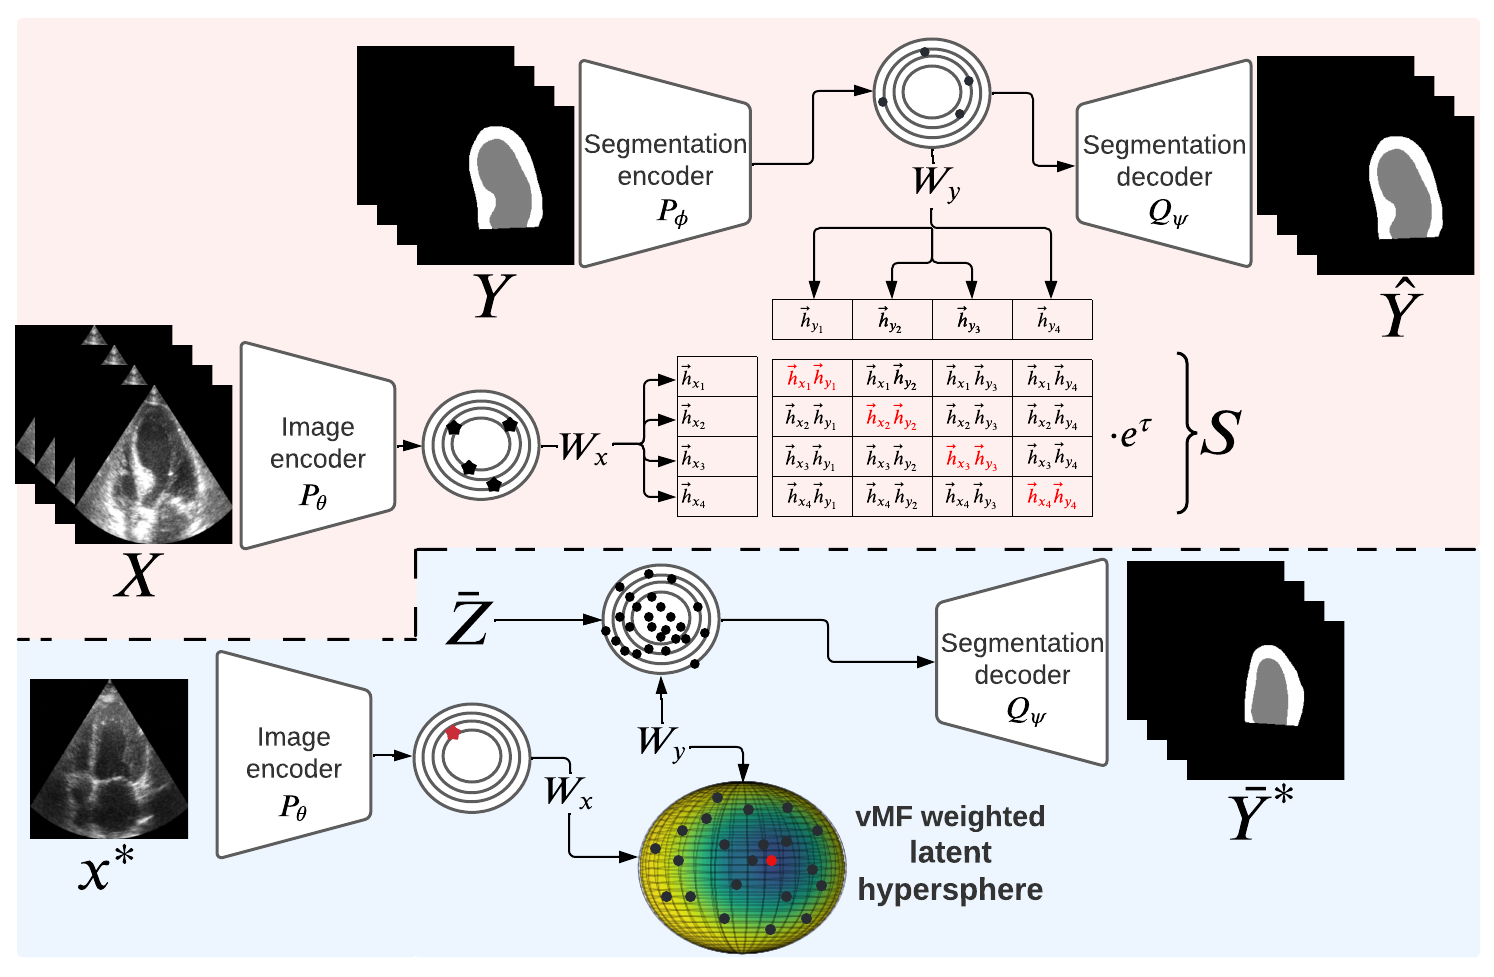

CRISP - Reliable Uncertainty Estimation for Medical Image Segmentation More Less

We propose CRISP, a CLIP-like contrastive image–segmentation representation that learns a joint latent space of images and valid segmentations, then uses similarity to many stored latent vectors to produce anatomically consistent uncertainty maps.

Abstract

Accurate uncertainty estimation is a critical need for the medical imaging community. A variety of methods have been proposed, all direct extensions of classification uncertainty estimations techniques. The independent pixel-wise uncertainty estimates, often based on the probabilistic interpretation of neural networks, do not take into account anatomical prior knowledge and consequently provide sub-optimal results to many segmentation tasks. For this reason, we propose CRISP a ContRastive Image Segmentation for uncertainty Prediction method. At its core, CRISP implements a contrastive method to learn a joint latent space which encodes a distribution of valid segmentations and their corresponding images. We use this joint latent space to compare predictions to thousands of latent vectors and provide anatomically consistent uncertainty maps. Comprehensive studies performed on four medical image databases involving different modalities and organs underlines the superiority of our method compared to state-of-the-art approaches.